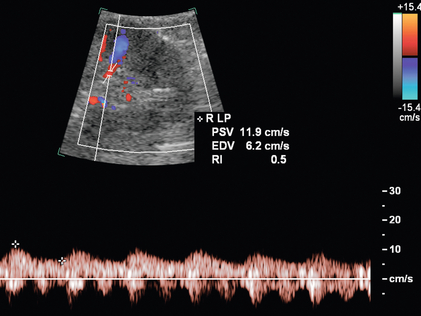

Для прямой спектральной допплеровской диагностики РАС были предложены различные критерии, что вызвало разногласия. PSV более 200 см/с ( рис. 9-12 ) был предложен для допплеровской диагностики уменьшения диаметра почечной артерии на 60%. В недавнем метаанализе PSV был лучшим критическим фактором в диагностике РАС с чувствительностью и специфичностью 85% и 92% соответственно. 29 Соотношение PSV почечной артерии и PSV аорты (RA/Ao) является еще одним критерием, предлагаемым для диагностики РАС. Соотношение RA/Ao PSV более 3,5:1 ( рис. 9-13 ) предполагает значительный уровень РАС, обеспечивая чувствительность 91% и специфичность 91%. Повышенное соотношение пиковой систолической скорости почечной артерии к систолической скорости дистальных почечных артерий также было предложено в качестве критерия диагностики РАС. Одно исследование 187 почечных артерий с ангиографической корреляцией также показало, что абсолютная почечная междолевая скорость PSV менее 15 см/с приводила к чувствительности и специфичности 87% и 91% соответственно для допплеровской диагностики 50% стеноза.Цзянь-Чу и др. недавно изучили влияние атеросклероза и возраста на параметры допплерографии для диагностики РАС и предполагают, что использование диагностических порогов почечно-аортального соотношения и почечно-междолевого соотношения различается у пациентов старше и моложе 46 лет. На другие сонографические критерии в их исследовании возраст пациентов существенно не влиял.